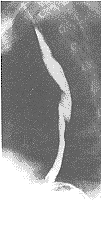

摘 要:目的 探讨在上胃肠道双对比造影检查中加用吸水试验,对胃食管返流的X线诊断价值。 材料与方法 219例吸水试验与322例非吸水试验者(即仅作通常的双对比造影)比较。 结果 吸水试验组与非吸水试验组中胃食管返流的检出率分别为41.55%与18.63%,前者较后者高出2.23倍。 结论 在日常上胃肠道X线检查中加用吸水试验,在诊断胃食管返流方面检出率明显增高,且简便、安全、省时、无需添加任何设备,可作为胃食管返流诊断的首选方法。